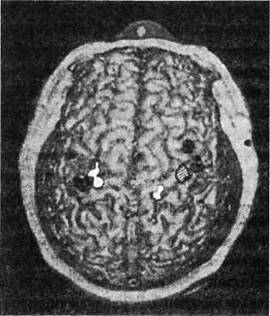

Независимо от того, какая из этих двух теорий — отращивание новых нервных ответвлений или обнаружение подавляемых сигналов — верна, во всем этом есть важная информация для медицины. Целым поколениям студентов-медиков твердили, что триллионы нейронных связей мозга закладываются во время внутриутробного развития и в раннем детстве, в то время как мозг взрослого теряет способность образовывать новые связи. Такое отсутствие пластичности, отсутствие способности восстанавливать или принимать новую форму часто использовалось как оправдание, когда пациентам говорили, почему им следует ожидать лишь очень небольшого восстановления функций после инсульта или травматического повреждения мозга. Наши наблюдения решительно опровергли эту догму, в первый раз показав, что даже основные карты чувствительности мозга взрослого человека могут изменяться на расстоянии в несколько сантиметров. Нам удалось использовать технику сканирования головного мозга, чтобы непосредственно показать правоту нашей теории: мозговые карты Виктора изменились так, как и было предсказано (рис. 1.3).

Вскоре после того, как наши данные были опубликованы, доказательства, подтверждающие и расширяющие эти открытия, стали поступать от многих исследовательских групп. Два итальянских исследователя, Джованни Берлукки и Сальваторе Альоти, выявили, что после ампутации пальца обнаружилась «карта» одного-единствен-

Рис. 1.3. Карта МЭГ (магнитоэнцефалограф) поверхности тела у пациента с ампутированной правой рукой. Заштрихованная область - кисть, черные области -лицо, белые области - верхняя часть руки. Обратите внимание, что область, соответствующая правой кисти (заштрихованная), отсутствует в левом полушарии, но этот участок активируется, когда дотрагиваются до лица или верхней части руки